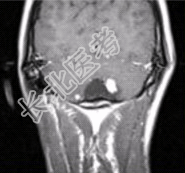

- [材料题] 男性,20岁。恶心、呕吐3d,剧烈头痛加重1d入院。MRI显示小脑下蚓部长T₁、长T₂信号影,病变可见结节状明显强化,如下图。

- 简答题1、请问该患者可能的诊断是什么?

- 简答题2、请问该病与VHL的关系是什么?